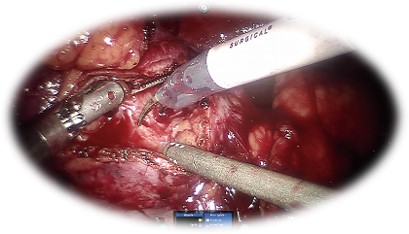

Prostatectomia radicală robotică:

• Standardul de aur în tratamentul chirurgical al cancerului prostatic localizat

• Presupune îndepărtarea glandei prostatice împreună cu veziculele seminale și ganglionilor regionali

• Rata complicațiilor intra și postoperatorie redusă, cu sângerare minimă

• Recuperare rapidă cu spitalizare redusă

• Calitate foarte bună a vieții

• Vizualizare 3D , 10x

• Eliminare tremor

• 7 grade libertate pentru instrumente